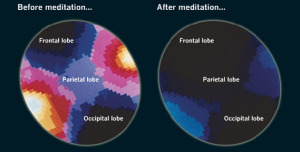

1. Scientists are learning more annually about the ways that meditators’ brains are different than non-meditators:

image from http://www.exploratorium.edu

Conclusions from above: meditation activates parts of our brain that ordinary brain activities do not.

2. Insight or Vipassana (Vipashana) meditators’ brains have been studied most. Here are some pictures to show how much that type of meditation changes the brains of Insight meditators:

image from http://www.nmr.mgh.harvard.edu

3. How else does meditation change one’s brain?

image from expanded–consciousness.blogspot.com

Meditators’ brains have thicker cortical areas and other parts are also strengthened unusually by meditation. Our brain waves are different even when we are not meditating. Really.

13. Here is that PET scan, again, of a meditating brain. Notice what parts are “activated” (by colors):

image from uonews.uoregon.edu

Now you begin to see more clearly how concussions impact meditation?

14. Our brains should look and function this way when we meditate:

image from blog.bufferapp.com

I sorely miss the feelings of “after,” calmness and joy which I normally would experience all day long. Awful losses, here. Luckily, purports to be temporary.

15. In conclusion, this quote incorporates the research I found and speaks to my particular injuries to explain why I can’t meditate and the effects of that on me: “The two important areas of the brain that feature prominently in meditation research are the frontal lobes, located in the area of the forehead, above the eyebrows and the limbic system which is deep inside the centre of the brain. Generally speaking, these two areas function and interact to influence our behavior, emotions, thinking, and what we’re going to do with our life. In other words together they have a profound influence on our personality, who we are and how we feel. The other parts of the brain [featured in meditation research] are the parietal lobes, at the top of the head, which primarily deals with the physical body, the occipital lobes at the back of the head that deal mostly with vision and the temporal lobes, above the ears, which deal with auditory information.”